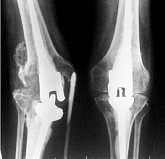

Еndoprosthesis of knee joint

In the late stages of arthrosis of the knee joint, accompanied by a pronounced restriction of the volume of movements, constant intense pain, deformity of the limb, the only way to recover is to replace the affected joint with an artificial joint - arthroplasty.

This method allows you to return the correct form of the limb, the full volume of movements in the joint, relieve the constant pain and crunch during movements and, as a result, significantly improve the patient's quality of life.

Below are presented X-ray photographs and photographs, illustrating the amount of motion in the affected joint before and after surgery.